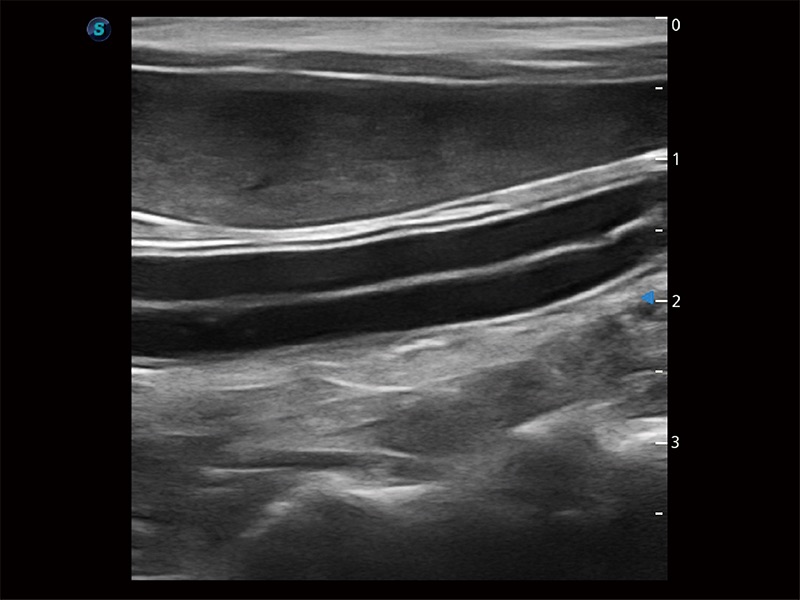

为精细结构及组织边缘提供高清晰度的图像和更大的成像视野。帮助减轻医生的用眼疲劳,快速精准获得测量的数据。

无论在暗室还是明亮的环境下,都能提供出色的对比分辨率、图像清晰度和鲜艳的色彩。

防炫光和防指纹超大触摸屏,支持角度可调节。